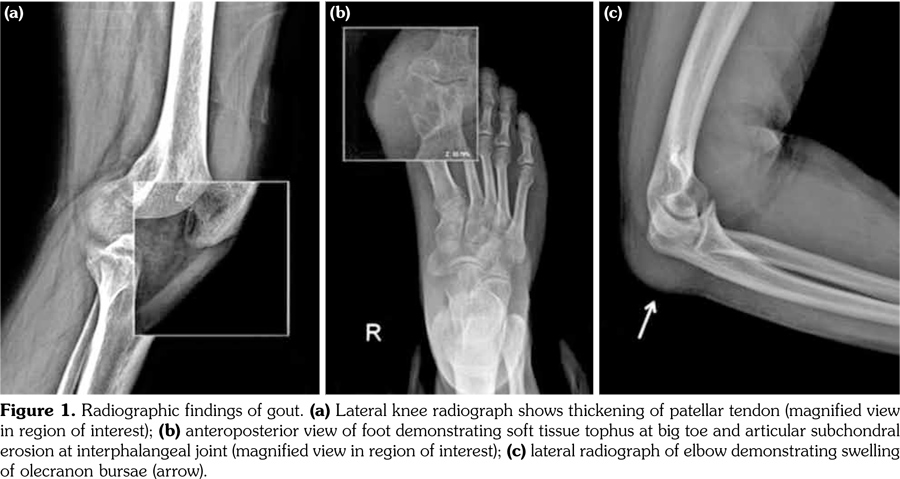

Gout is a clinical disorder resulting from urate crystal deposition.(1) Tendinopathy and enthesopathy are extra-articular gout manifestations. The common sites involved in knee are the popliteus tendon, cruciate ligaments, and quadriceps tendon.(2) Although patellar tendon has been mentioned as a possible involvement site, to our knowledge, only three case reports exist in the literature, two of which were reported in triathletes mimicking patellar tendonitis precipitated due to prolonged exercises.(3-5) In this article, we report a 34-year-old male patient with eight years history of gout who presented with one week history of pain and swelling of extremities. He underwent excision of the olecranon bursae and biopsy from the tophus involving first toe three years ago. Recurrent gouty attacks were treated with nonsteroidal anti-inflammatory drugs, colchicines (1 mg/day), and analgesics. Serum uric acid level was 11.9 mg/dL, C-reactive protein was 18.2 mg/dL. Allopurinol had been discontinued due to elevated liver enzymes (alanine transaminase: 132 U/L; aspartate aminotransferase: 85 U/L). Physical examination demonstrated tophi overlying the toe, and tenderness over the caudal aspect of patella. The patellar tendon was slightly thickened on radiographs. Soft tissue tophus at the interphalangeal joint causing adjacent

erosive changes, and swelling of olecranon bursae were seen (Figure 1). Magnetic resonance imaging showed fusiform mass-like thickening of the proximal patellar tendon, measuring 30x16 mm, with intermediate signal on T1 weighted and T2 weighted images. Edema of the tendon at insertion and patellar cortical irregularities not seen on radiograms were demonstrated (Figure 2).